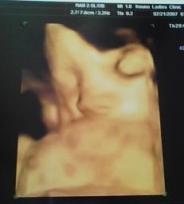

昨日、妊婦検診に行ってきました~☆2週間前から400グラムほど成長していて、推定体重は1900グラム。このままのペースだと、子供は大きめになりそう・・・(- -; 今まで検診の時にはエコー写真しか見たことがなかったのですが、4D検診というのができるってことで、初チャレンジしてみましたヽ(*・ω・)人(・ω・*)ノ 初めて見たわが子の立体的な顔☆顔を隠してなかなか見せてくれなかったんですが、(誰に似たのかあまのじゃくなのか・・・?!)なんとかこの画像を撮ることができました~☆ 旦那に見せたら、「こんなの見れるんだね!明日職場に持っていってみんなに見せよう!」といって、今日は職場に写真を持って行きました(笑)